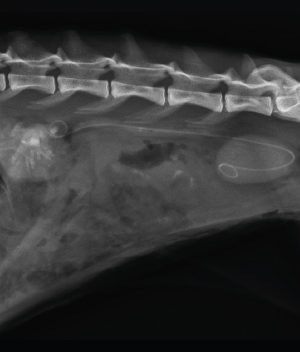

Double-pigtail Ureteral Stent

고양이 요관 결석에 실시할 수 있는 중재술 중 하나로 SUB 다음으로 추천됩니다. SUB와는 달리 지속적인 관리가 필요하지 않지만 고양이에 적용 시 평균 수술 시간이 길다는 단점이 있습니다.